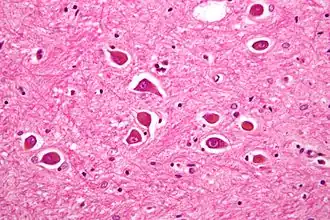

Pathogenèse

La cause première de l'encéphalopathie hépatique est l'association d'une insuffisance hépatocellulaire et d'un shunt porto-systémique causé par l'hypertension portale.

Une relation certaine existe entre l'encéphalopathie hépatique et l'augmentation de l’ammonium sérique, due à l'accumulation de son précurseur, la glutamine, qui aurait un effet toxique direct sur le cerveau[5]. La glutamine est théoriquement transformée en glutamate et en ammonium puis en urée par le foie. En cas de défaillance de cet organe, le taux sanguin de ces métabolites augmente fortement. Par ailleurs, l'ammonium est également métabolisé dans les cellules musculaires, l'atrophie musculaire pouvant donc aggraver la situation[6]. Un syndrome inflammatoire peut en aggraver les symptômes[7].

D'autres métabolites comme les mercaptans seraient aussi neurotoxiques. D'autre part, certains neurotransmetteurs dégradés dans le foie, comme le GABA, pourraient se trouver en excès dans le cerveau et participer à l'altération du niveau de vigilance. Enfin, certains arguments plaident en faveur d'un rôle possible du manganèse ; en effet, l'IRM encéphalique montre des images traduisant des dépôts de cet élément dans le globus pallidus[8].